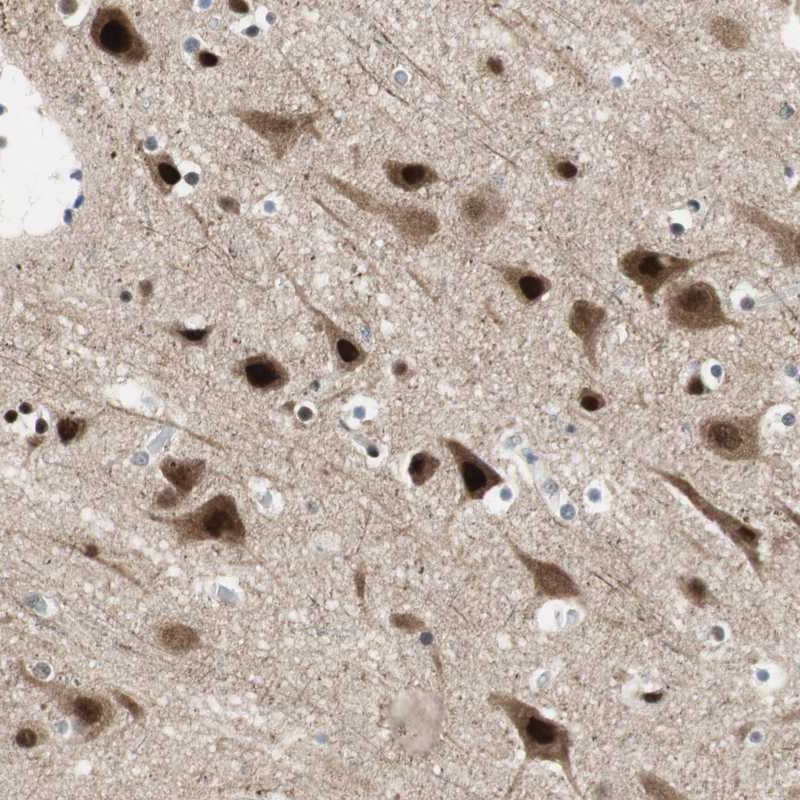

Immunohistochemistry is used for validating antibody reliability by assessing staining pattern in 44 normal tissues. Validation scores include Enhanced, Supported, Approved and Uncertain.

Immunohistochemical staining of human cerebral cortex shows strong nuclear and cytoplasmic positivity in neuronal cells.